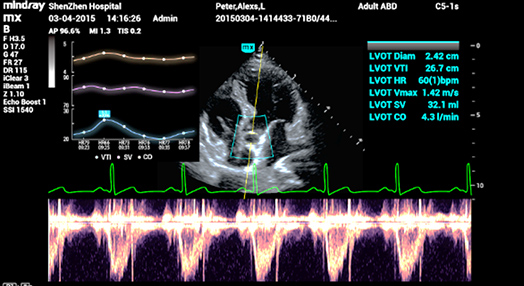

2Smart VTI

Medici├│n autom├Ītica de la VTI (integral de velocidad en funci├│n del tiempo) y CO (gasto card├Łaco) para una evaluaci├│n r├Īpida de la funci├│n card├Łaca. Localizaci├│n autom├Ītica de la caja de color y la l├Łnea de muestra de PW en tiempo real. Gr├Īfico de tendencias de par├Īmetros sobre CO, SV y VTI para guiar la toma de decisiones.

2